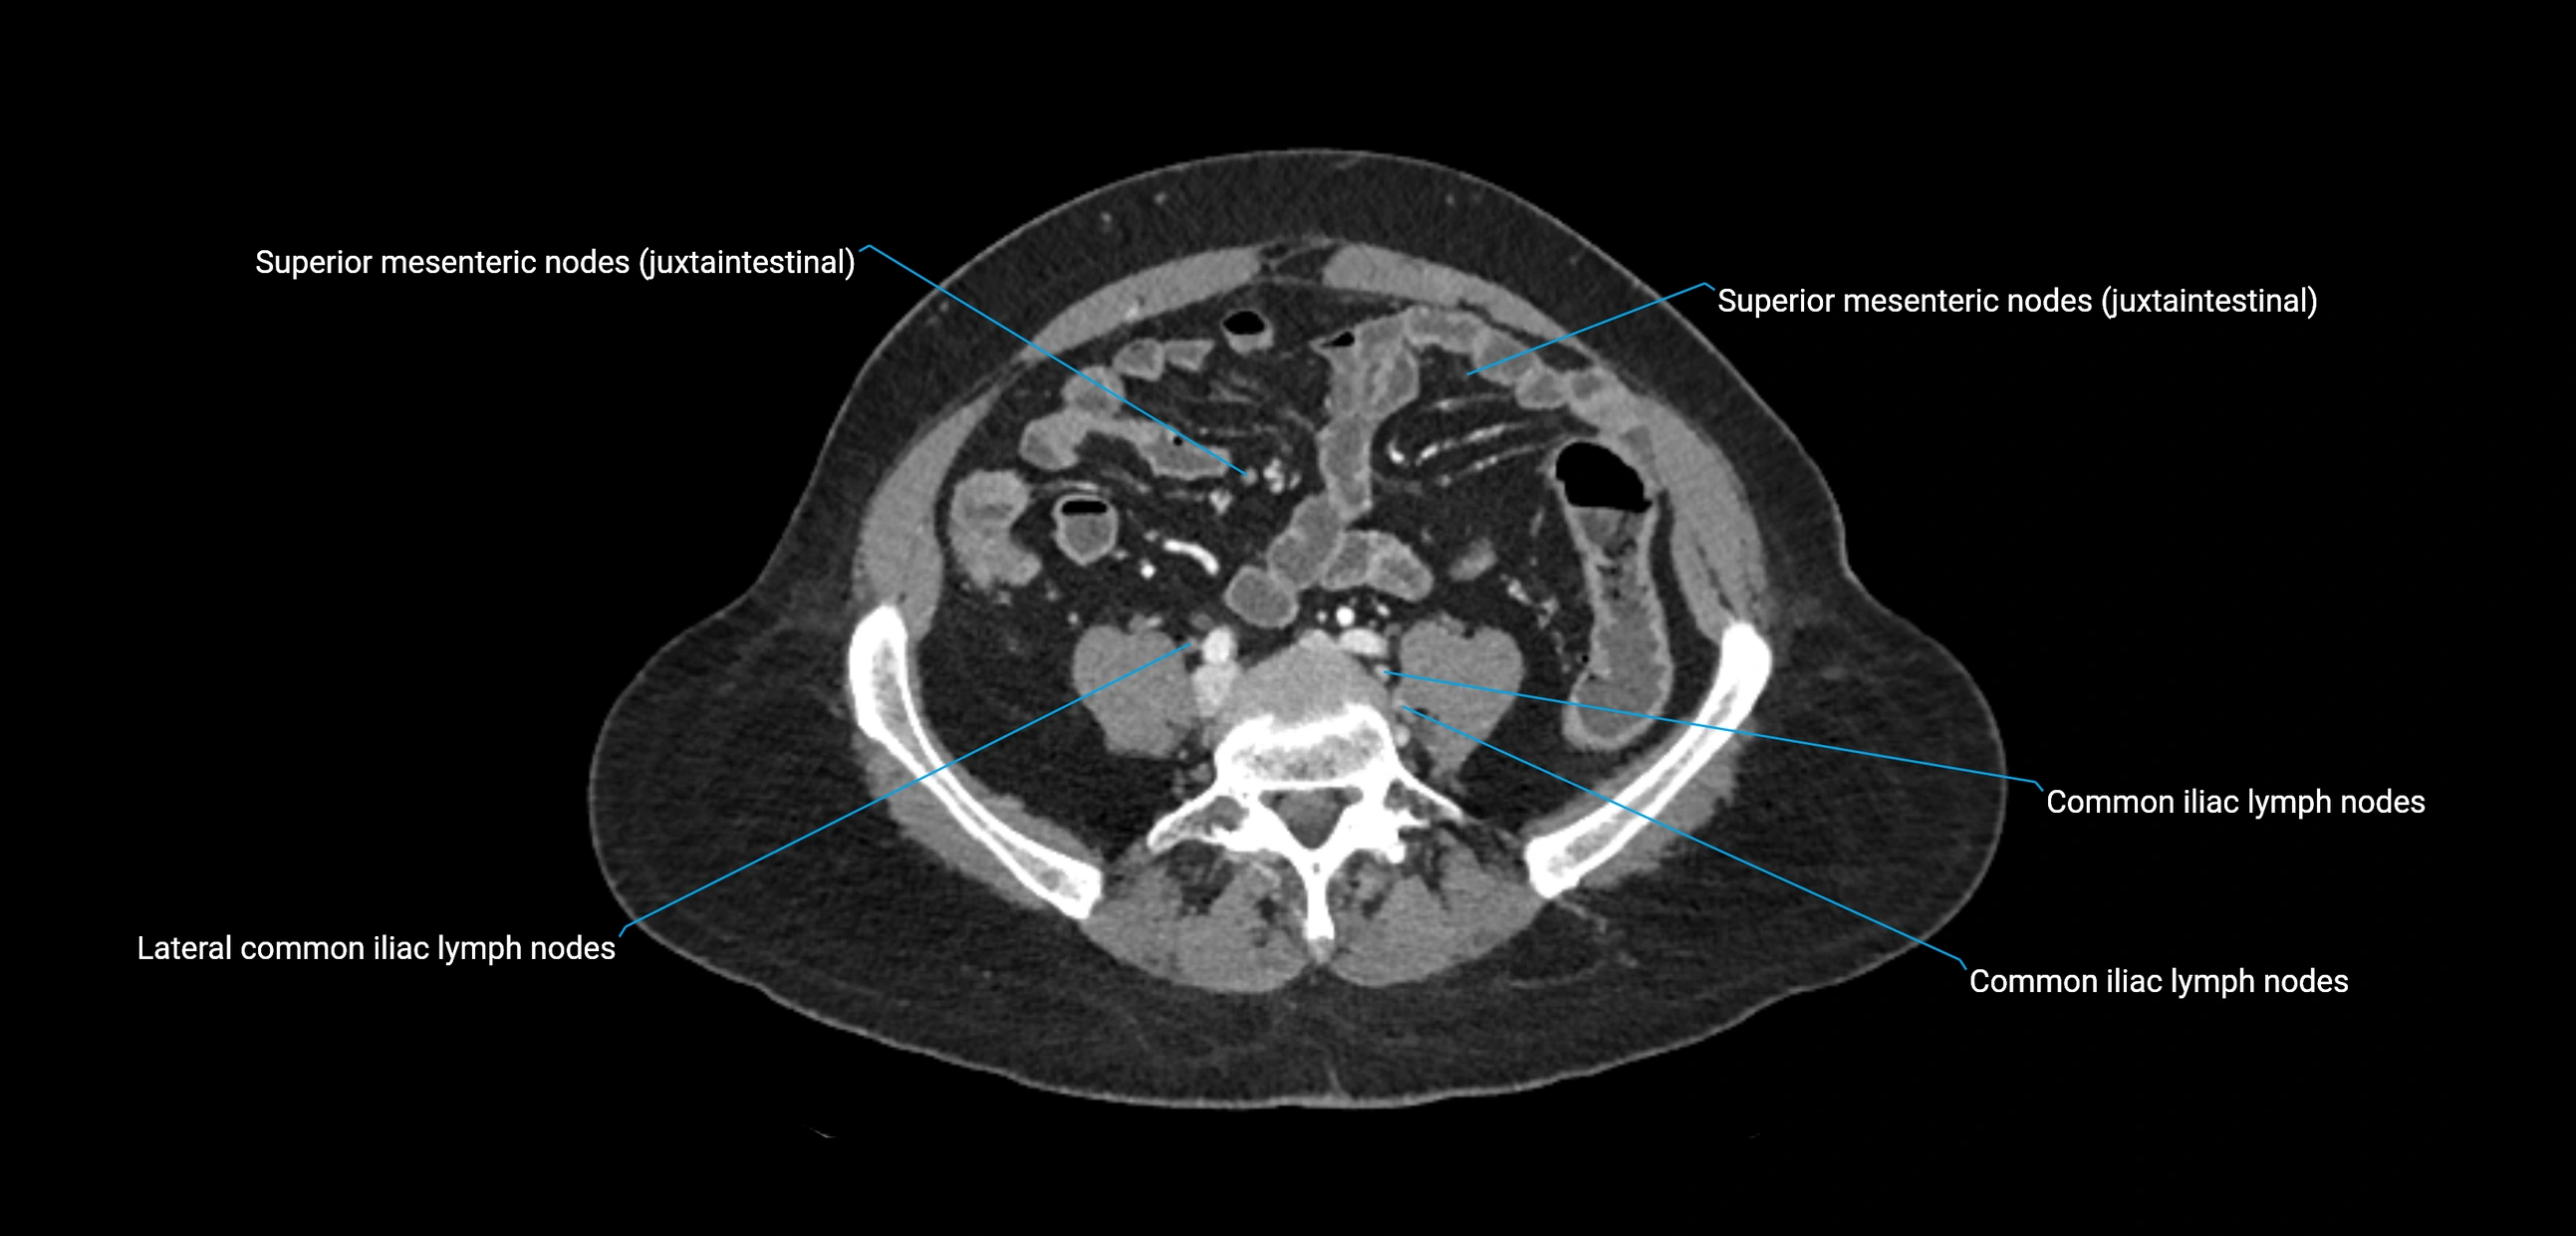

CT Appearance

CT Pre-Contrast:

• Nodes appear as soft-tissue density nodules adjacent to the aorta and IVC

• Calcification may be seen in chronic infections (e.g., tuberculosis)

CT Post-Contrast:

• Normal nodes enhance homogeneously

• Malignant nodes may show heterogeneous enhancement, central necrosis, or conglomerate formation

• Size >1 cm short axis is suspicious, though morphology and distribution are equally important

CT Venography (CTV):

• Demonstrates nodal encasement or compression of adjacent vessels (aorta, IVC, renal veins)

• Useful in staging testicular and ovarian malignancies

• Provides 3D reconstructions for retroperitoneal lymph node dissection planning

CT image

image